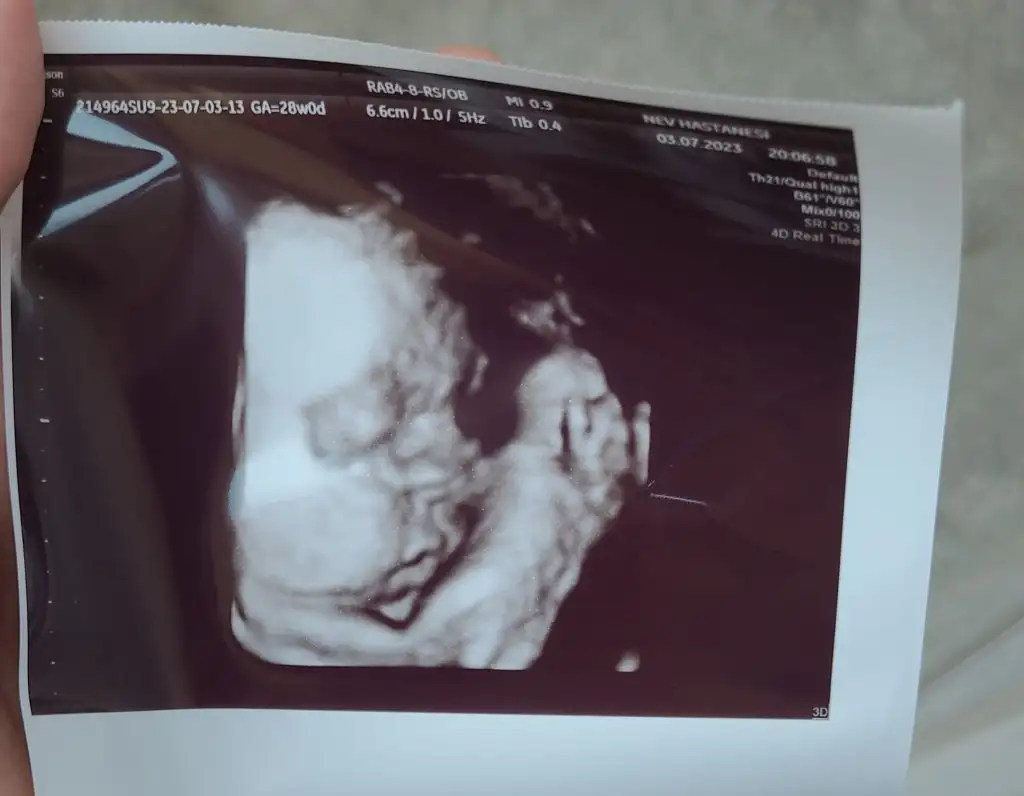

41 kere maşallahKızlaaar merhaba, ben kontrolden çıktım maalesef boğazlarım iltihaplanmış düşük doz antibiyotik yazdı kbb doktoru. Ama kızım çok şükür iyiymiş. Kan plesanta koruyucuğu diye birşey varmış. Biz hasta olsak bile bebek bu sayede sağlıklı kalıyormuş. Ateşimiz çıkarsa bebek etkilenmeye başlıyormuş.içim çok rahatladı. Bugün 28+0ız. 1400gram olmuşuz. Yanaklarımıza ne demeli peki, tam tospik olmuşuzbir maşallahınızı alırız

Oy maşallah sizeKızlaaar merhaba, ben kontrolden çıktım maalesef boğazlarım iltihaplanmış düşük doz antibiyotik yazdı kbb doktoru. Ama kızım çok şükür iyiymiş. Kan plesanta koruyucuğu diye birşey varmış. Biz hasta olsak bile bebek bu sayede sağlıklı kalıyormuş. Ateşimiz çıkarsa bebek etkilenmeye başlıyormuş.içim çok rahatladı. Bugün 28+0ız. 1400gram olmuşuz. Yanaklarımıza ne demeli peki, tam tospik olmuşuzbir maşallahınızı alırız

Maşallah annesi sanada geçmiş olsunKızlaaar merhaba, ben kontrolden çıktım maalesef boğazlarım iltihaplanmış düşük doz antibiyotik yazdı kbb doktoru. Ama kızım çok şükür iyiymiş. Kan plesanta koruyucuğu diye birşey varmış. Biz hasta olsak bile bebek bu sayede sağlıklı kalıyormuş. Ateşimiz çıkarsa bebek etkilenmeye başlıyormuş.içim çok rahatladı. Bugün 28+0ız. 1400gram olmuşuz. Yanaklarımıza ne demeli peki, tam tospik olmuşuzbir maşallahınızı alırız